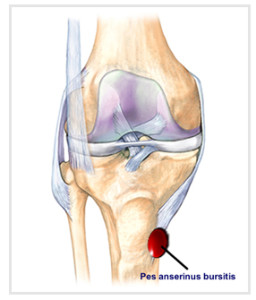

Заболевание сустава: симптомы и лечение

Раздел: Фотодневник открытий